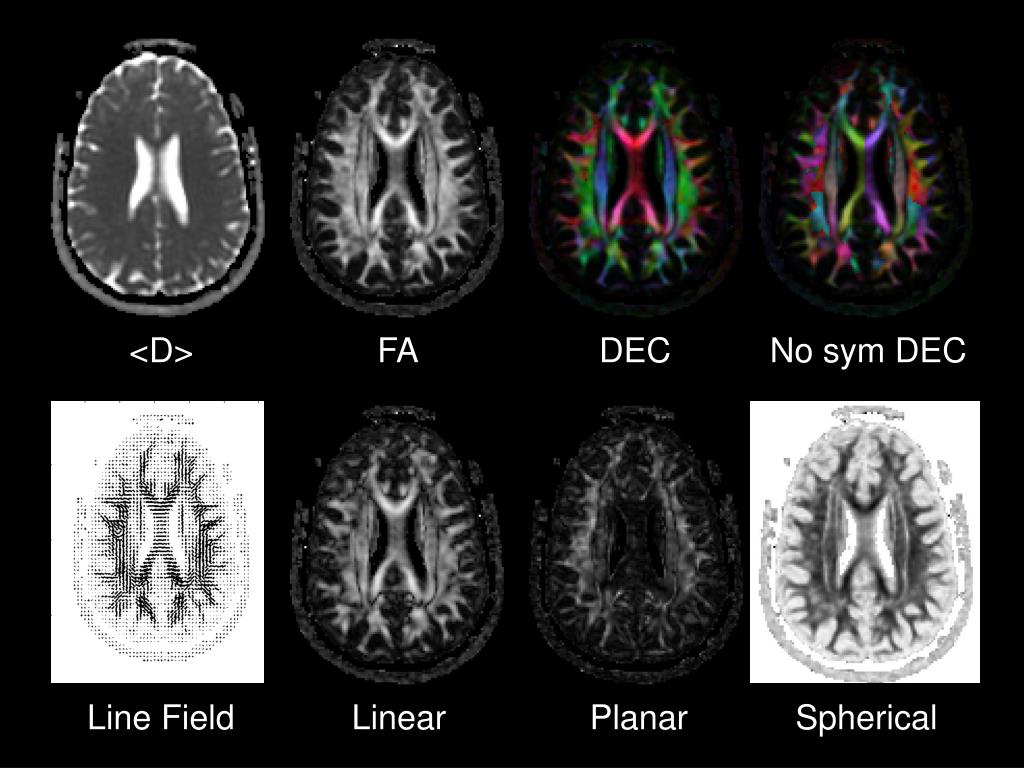

35. <D> FA DEC No sym DEC Line Field Linear Planar Spherical

36. Applications of DTI • Traumatic Brain Injury • Alzheimer’s Disease • Amyotrophic Lateral Sclerosis • Niemann-Pick type C Disease • Dementias • Connectivity • Cerebral Ischemia (Stroke) • Brain Cancer and Effects of Radiotherapy • Multiple Sclerosis • Epilepsy • Metabolic Disorders • Normal Brain Maturation and Aging